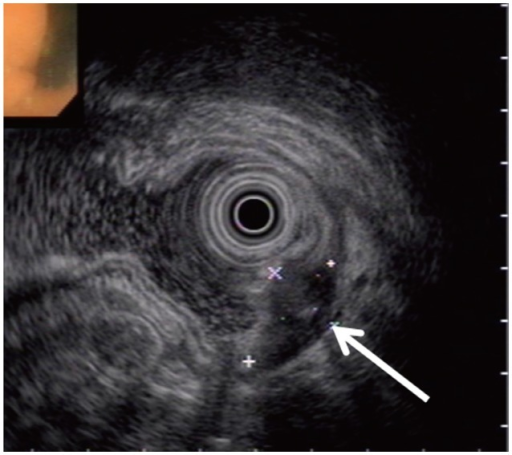

Small-Object Detection [Uncaptioned image] Question: Considering the mass’s visual characteristics in the provided image and its relationship to surrounding structures, which feature best supports the conclusion that this is a pathologically significant tiny focus rather than an artifact or normal variation? Options: A) The ovoid, heterogeneous hypoechoic focus with small echogenic foci centered in the submucosa and muscularis propria supports a true pathologic lesion. B) The ovoid, heterogeneous hypoechoic focus with small central echogenic foci confined to the mucosal layer is diagnostic of a true pathologic lesion. C) The ovoid, heterogeneous hypoechoic focus with central echogenic foci abutting only the muscularis mucosae suggests a focal pathology and therefore supports a true lesion rather than benign variation. D) The ovoid, heterogeneous hypoechoic focus with small central echogenic foci confined to the mucosal layer and superficial submucosa is indicative of a true pathologic lesion rather than an artifact. E) The small ovoid, heterogeneous hypoechoic focus with punctate echogenic foci localized predominantly to the mucosal and superficial submucosal layers is most consistent with a true pathologic lesion rather than an artifact. Answer: A Explanation: The mass shows an ovoid and heterogeneous hypoechoic focus with several small echogenic spots inside it. These features are centered in the submucosa and muscularis propria, which are deeper wall layers that do not normally contain such discrete structures. Artifacts on endoscopic ultrasonography usually do not form a stable ovoid shape, do not show internal echogenic foci arranged in a consistent pattern, and do not remain confined to specific wall layers. Normal variation of the gastric wall also does not create a sharply outlined hypoechoic mass in these deeper layers. Because the lesion has a defined shape, internal components, and a location that matches a true subepithelial abnormality, option A best supports the presence of a real small lesion rather than an artifact or normal tissue change.